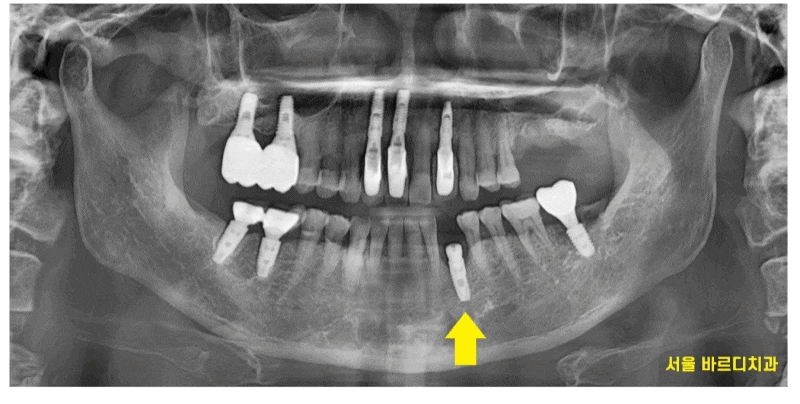

24.04.16

x-ray 상에서도 잇몸이 많이 녹아있네요ㅠㅠ

잇몸뼈가 많이 녹아

치아 뿌리만 겨우 붙잡고 있습니다.

붙잡고 있는게 얼마 없어

식사할때마다 흔들렸을꺼고

많이 불편하셨겠어요~